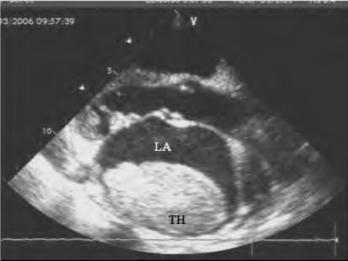

图15-3 左房血栓二维超声图

左室长轴切面见左房后壁及顶部附着不规则强弱不均的回声,边缘清楚,基底宽。TH:血栓,LA左房